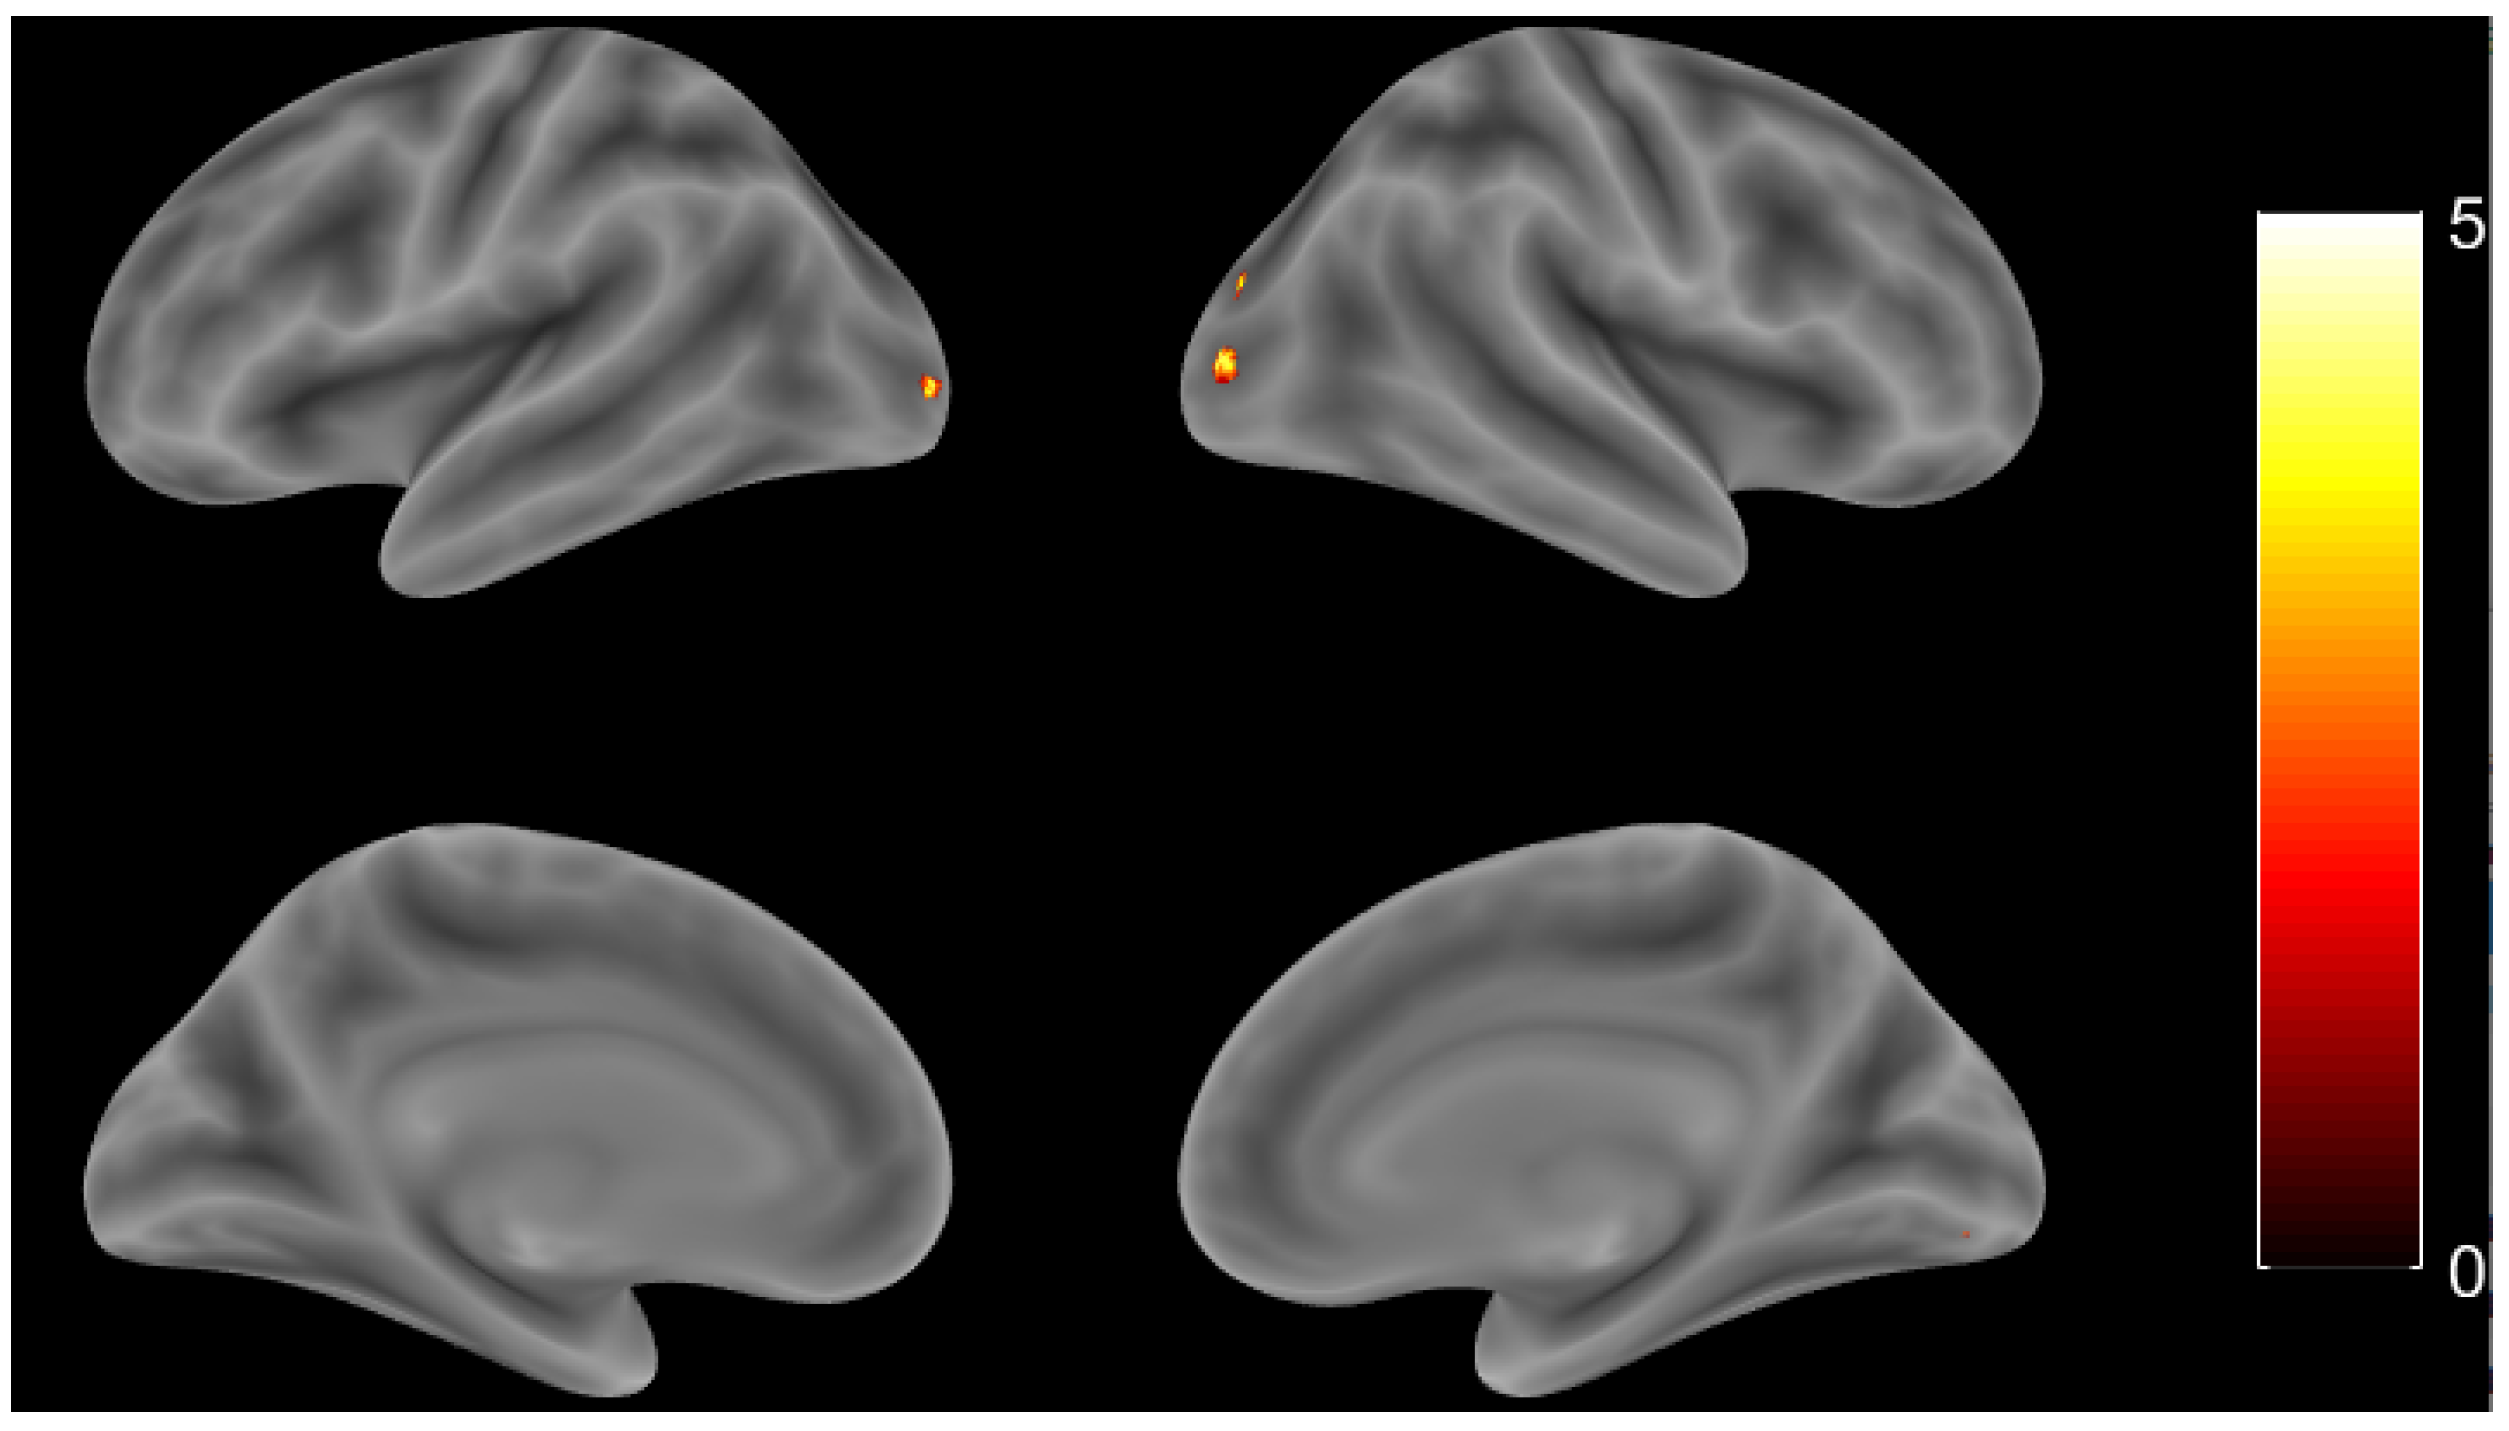

3.3. Group Comparison

3.3.1. Whole Brain Analysis

| Region Label | Extent | T Value | MNI Coordinate | ||

|---|---|---|---|---|---|

| x | y | z | |||

| R lingual gyrus | 138 | 5.034 | 24 | V82 | 6 |

| R cerebellum (crus 1) | 70 | 4.476 | 42 | V64 | V24 |

| L inferior occipital gyrus | 36 | 4.311 | V24 | V92 | 0 |

| R cerebellum (VI) | 42 | 4.192 | 24 | V78 | V18 |

| L cerebellum (VI) | 37 | 4.028 | V36 | V56 | V32 |

| L caudate | 10 | 3.971 | V14 | V28 | 26 |

| L cerebellum (VI) | 6 | 3.797 | V8 | V62 | V18 |

| R lingual gyrus | 9 | 3.716 | 14 | V86 | V8 |

| L middle occipital gyrus | 40 | 4.468 | V24 | V60 | 42 |

| L IFG (p. triangularis) | 6 | 4.284 | V52 | 24 | 30 |